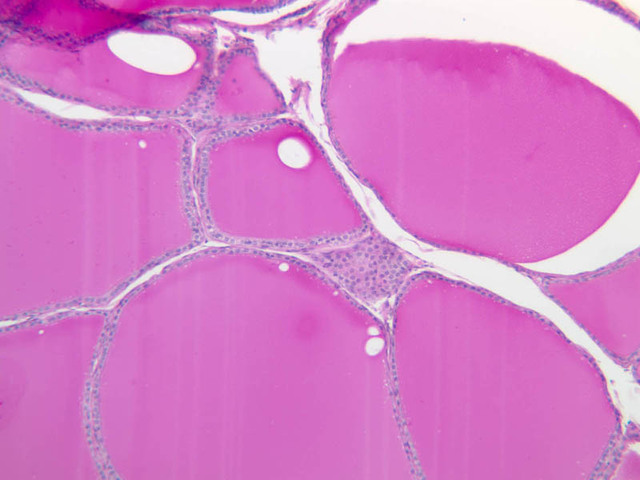

The thyroid gland (slide B-51, lead hematoxylin [10x, 20x, 40x, 40x]; B-52, H&E [10x-labeled, 20x, 40x-labeled, 40x]; B-53, PAS [2.5x, 10x, 20x, 40x]) consists of many closely packed, roughly spherical structures known as follicles, which are enclosed in a thick connective tissue capsule. Connective tissue septa extend from the capsule into the substance of the gland, carrying numerous blood vessels. Follicular cells are arranged as shells of simple cuboidal epithelium surrounding a gelatinous mass known as colloid. Look for a ring of epithelial cells around the homogeneous, pink-staining colloid. The cytoplasm of the follicular cells (principal cells) is faintly basophilic. The follicular cells secrete thyroglobulin, a glycoprotein, which is stored extracellularly in the colloid. In response to TSH, the follicular cells endocytose the colloid and hydrolyze it to form thyroxine. You can see where colloid has been resorbed because this process leaves small holes in the colloid adjacent to the follicular cells. These holes are known as resorption lacunae (B-52 [10x, 20x, 40xlabeled]). Very active follicles may exhibit a columnar epithelium and increased numbers of resorption lacunae. Between follicles, the stroma of the thyroid gland consists of a thin layer of connective tissue and a rich capillary network. Parafollicular cells (light cells or C cells) are located in the connective tissue between follicles or adjacent to follicular cells within follicles. When they lie within the follicular wall, the parafollicular cells do not reach the lumen. Parafollicular cells are slightly larger than the follicular cells and, in H & E preparations, have a more lightly stained cytoplasm (B-52, H&E [10x, 20x, 40x-labeled] [10x-labeled, 20x, 40x-labeled] [10x, 20x, 40x] [10x, 20x, 40x]; B-53, PAS [10x, 20x, 40x]). Parafollicular cells are readily identifiable in slide B-51 (stained with lead hematoxylin), where they appear as purplish-black structures in which the nuclei are difficult to discern (B-51 [10x, 20x, 40x-labeled]). These cells secrete calcitonin, which lowers serum calcium levels by inhibiting bone resorption and accelerating osteoid calcification.